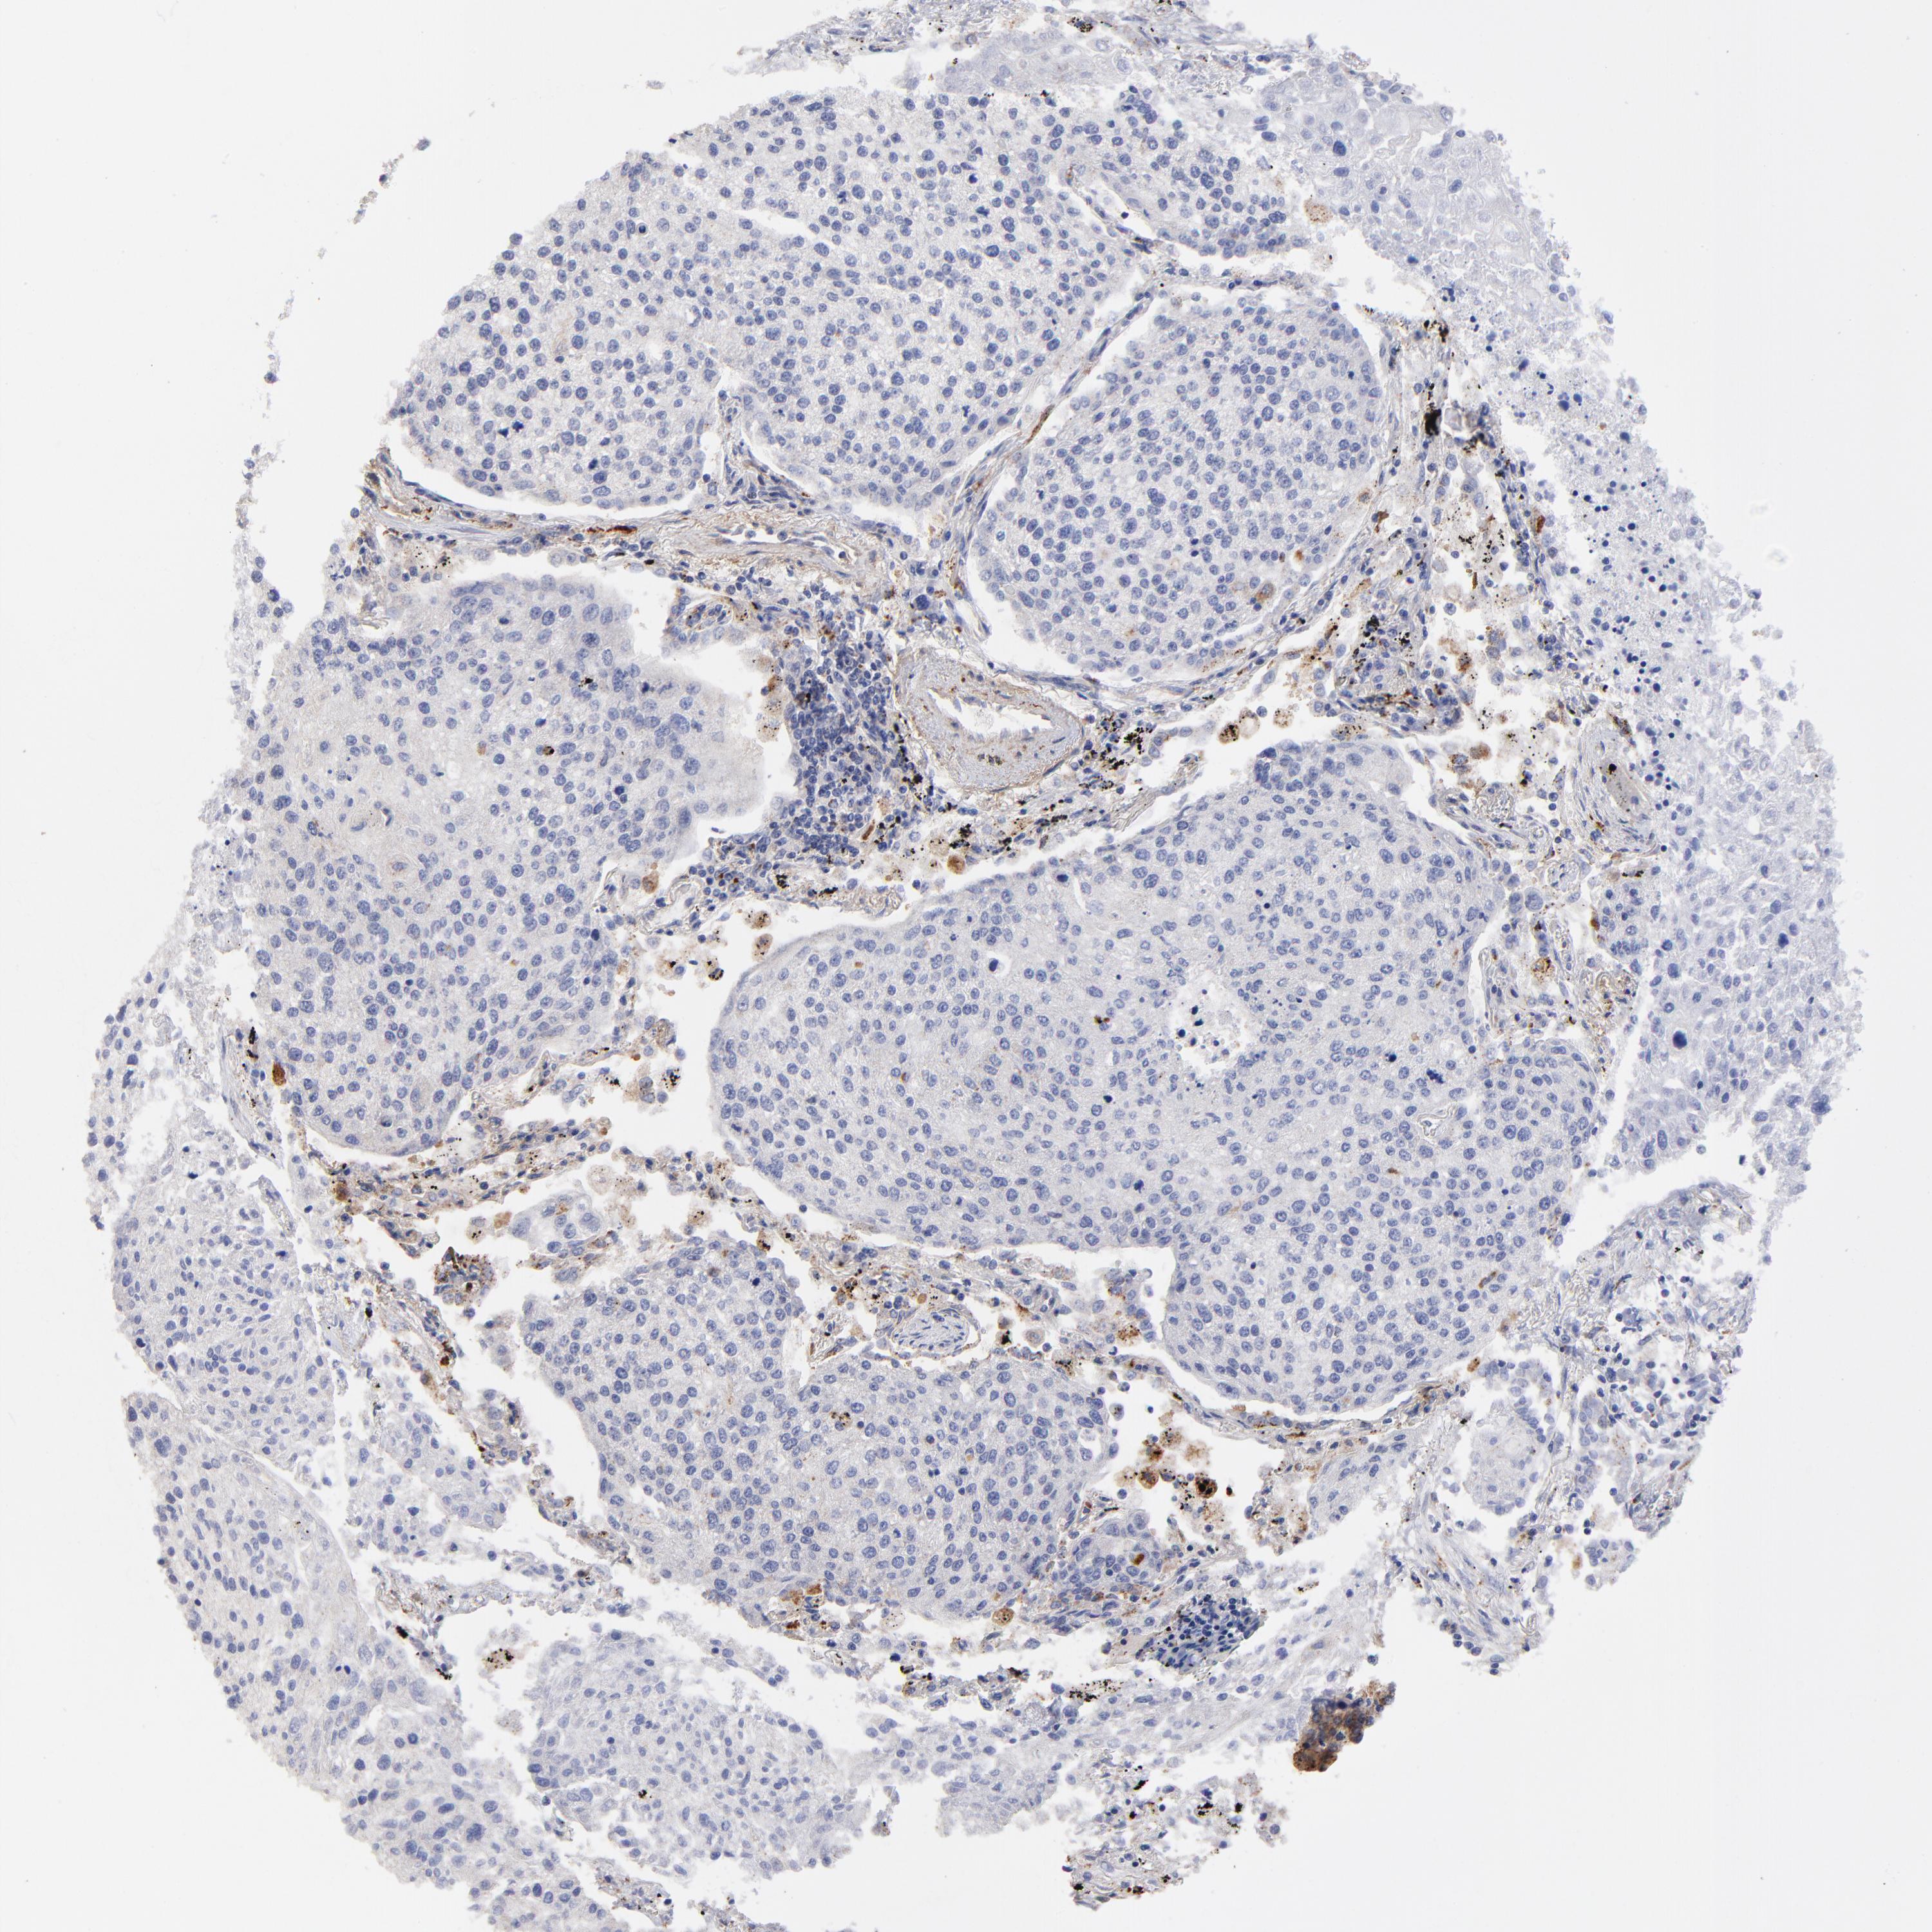

CANCER LUNG CANCER Show tissue menu